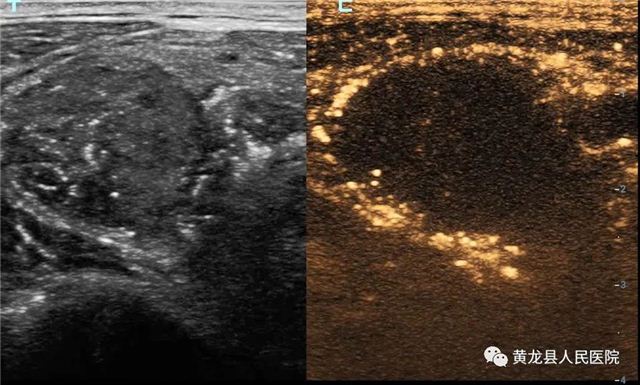

甲状腺结节术前造影

甲状腺结节术后造影